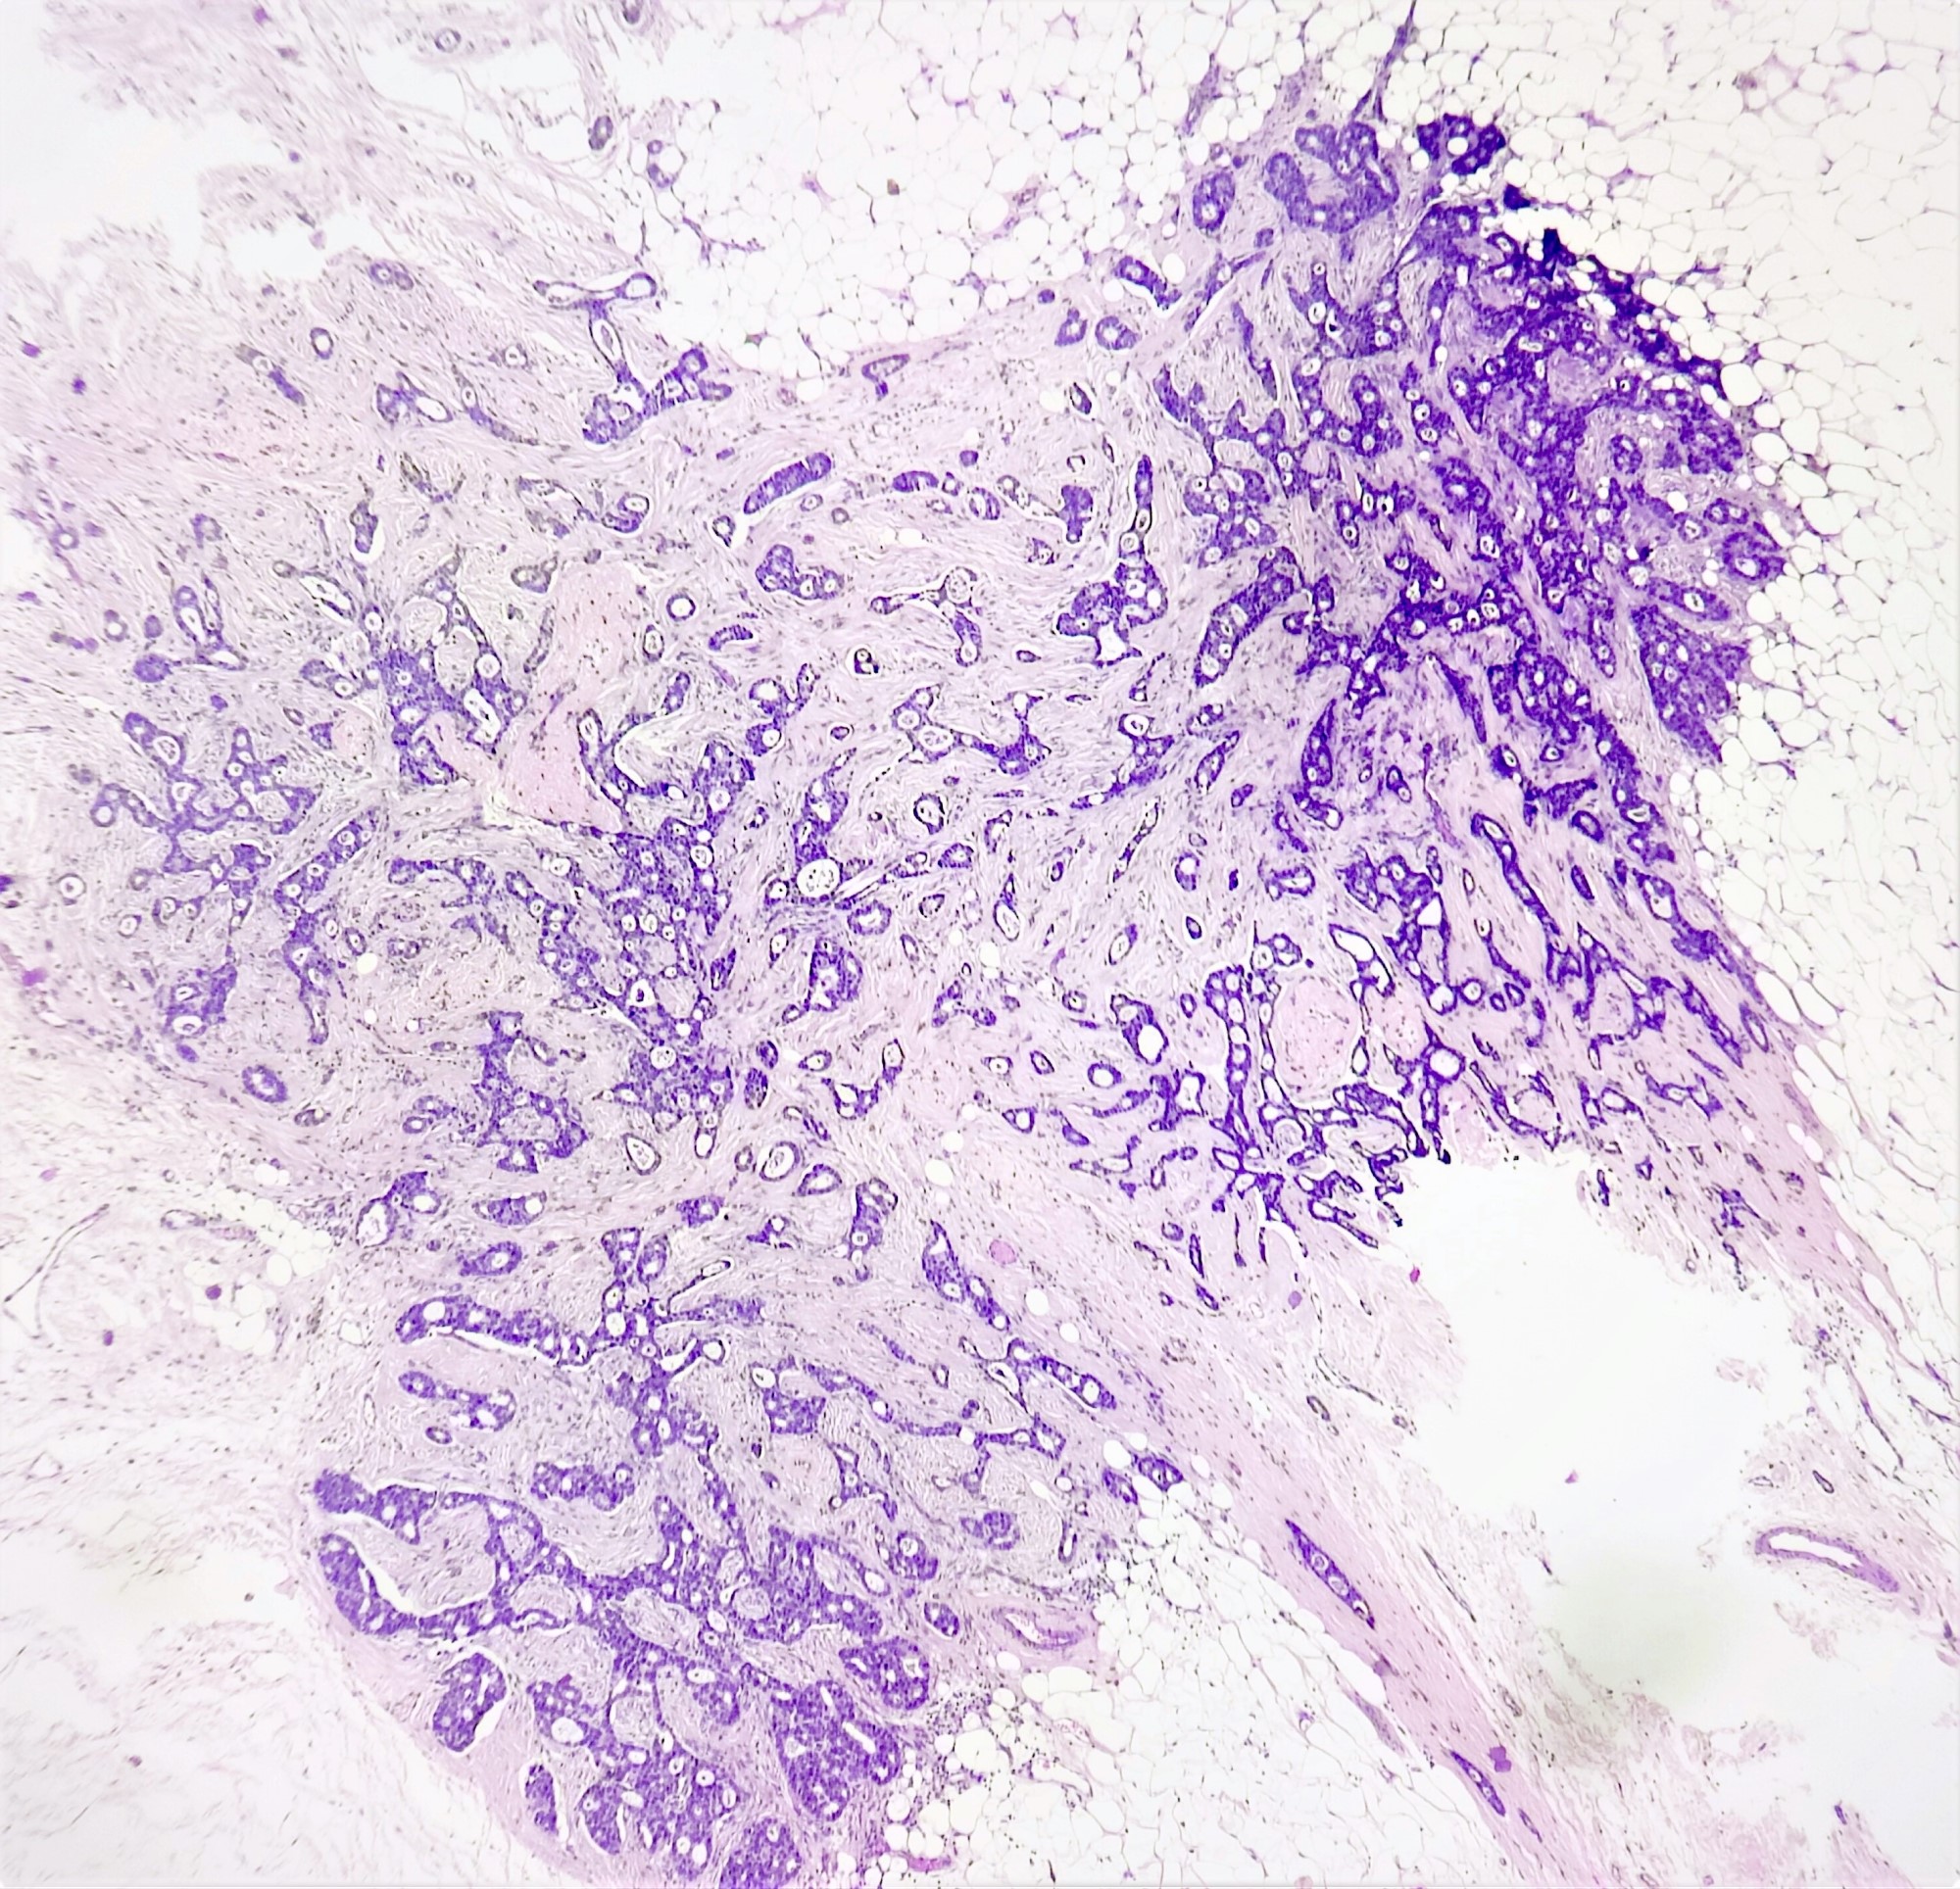

Microscopic (histologic) description

- Irregular cribriform growth pattern > 90% of cells

- Nuclear grade I pure ICC: > 90% cribriform pattern

- Mixed: 10 - 90% other morphological type, other than cribriform carcinoma

- Low grade: Nottingham grade 1 tumors

- Invasive islands or nests of malignant cells with round or angulated contours and well defined cribriform spaces formed by arches of epithelial cells; this gives a sieve-like appearance

- Tumor cells: small, mild / moderate pleomorphism, no nuclear atypia

- No / sparse mitotic activity

- Desmoplastic stroma

- Mucin positive secretion, microcalcifications in lumen

- Osteoclastic giant cells may be seen

- Myoepithelial cells absent

- Associated with cribriform ductal carcinoma in situ (DCIS)

Microscopic (histologic) images

Contributed by Sunitha Shankaralingappa, M.B.B.S, M.D., D.M.